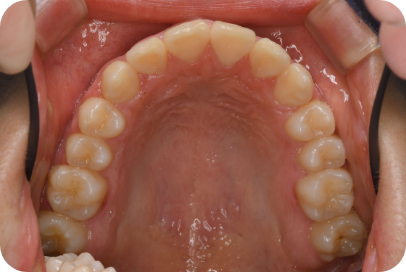

Tさん

Before

After

- 形態:狭いV型の上顎を丸くて広いU型に改善、歯ならび、咬み合わせの改善

- 機能:咀嚼嚥下トレーニング、口腔周囲筋トレーニング、姿勢改善